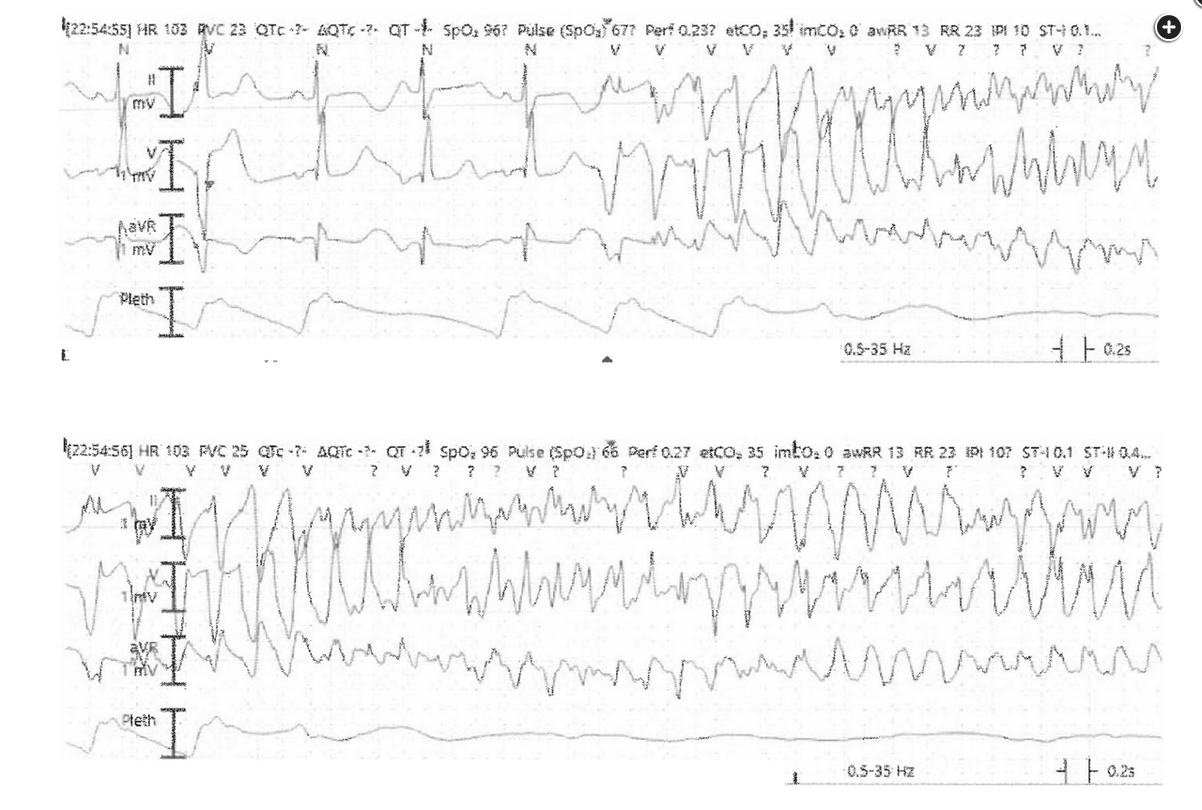

Figure 2 demonstrates a wide complex tachycardia with morphologically distinctive “twisting of the points” characteristic of torsades de pointes (TdP). The primary risk factor for this arrhythmia is marked QT interval prolongation on admission ECG in a patient with underlying structural heart disease and severe hypokalemia. In addition to addressing reversible risk factors for recurrent arrhythmia (ie, correcting potassium in this patient), treatment with IV magnesium is most appropriate at this time.

The primary mechanism leading to TdP is early depolarization (ie, a premature ventricular complex) during prolonged ventricular repolarization (ie, a long QTc interval, as in Figure 2). While the risk of malignant arrhythmia in the setting of prolonged QT interval is difficult to predict, QTc >500 ms or drug-induced increase of >30 to 60 ms should prompt concern. Magnesium inhibits cardiac myocyte calcium influx, suppressing automaticity and reducing early and late after-depolarizations. While prospective randomized clinical trials have failed to demonstrate that magnesium increases the rate of return of spontaneous circulation or survival after preor in-hospital cardiac arrest due to refractory ventricular fibrillation, guidelines continue to recommend its use in the setting of medication-induced TdP or marked electrolyte derangements. Aggressive correction of electrolytes and hypoxemia, discontinuation of offending agents, and pharmacologic or transvenous pacing to increase the heart rate should also be considered.